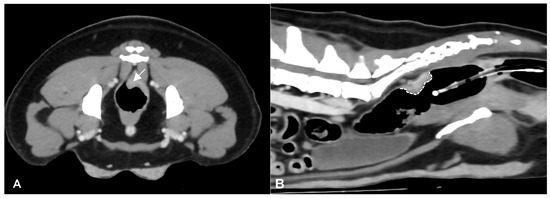

CT identified a colorectal lesion in all dogs. Specifically, 5 dogs had lesions localized at the colorectal junction, 3 at the descending colon, 1 at the transverse colon, and 1 at the anorectal junction. The characteristics of these lesions varied: 6 (Figure 1) dogs exhibited transmural, circumferential, asymmetric thickening of the wall, while 2 (Figure 2) cases (one adenocarcinoma and one carcinoma) displayed transmural, circumferential symmetric thickening. The leiomyosarcoma case was characterized by the presence of an exophytic mass (Figure 3).

Figure 1. Post-contrast CT images of a colorectal adenocarcinoma in a 5-year-old female Border Collie. Transverse (A) and sagittal (B) plane reconstructions are available. A transmural, endophytic, broad-based, asymmetric, heterogeneously enhancing thickening of the left dorsolateral aspect of the colorectal wall is noted (white arrow). In the sagittal plane, the craniocaudal extension of the lesion is evident (dotted white line). A Foley catheter is also visible within the gas-filled rectal lumen.